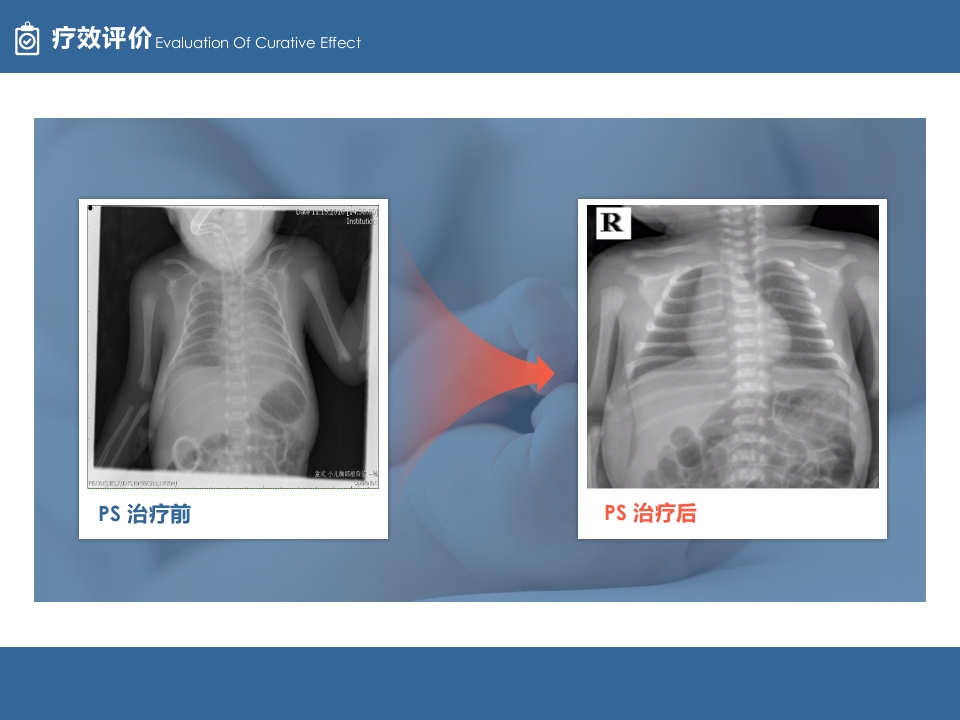

疗效评价 Evaluation Of Curative Effect

PS 治疗前

PS 治疗后